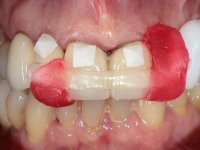

Paciente do sexo feminino, com 69 anos, não fumadora. Apresenta uma prótese combinada no maxilar superior. A porção fixa corresponde a uma ponte metalo-cerâmica de 4 elementos com os dentes 1.3/1.1 e 2.1 como pilares e o dente 1.2 como pôntico. A porção amovível corresponde a uma prótese esquelética de 5 elementos. A retenção da prótese esquelética é feita por um gancho no dente 1.4 e um “attachment tipo t” colocado no dente 2.1.

O estudo imagiológico para a colocação dos implantes, começou com a realização em laboratório de uma guia com dentes em sulfato de bário. Esta guia foi colocada em boca conjuntamente com marcas de referência coladas aos dentes, também em sulfato de bário. A guia foi estabilizada com cera mole. A TAC foi realizada com estas referências colocadas em boca. Após a realização da TAC foi feita uma impressão de arrasto em silicone. Esta impressão foi vazada a gesso em laboratório e posteriormente digitalizada. A digitalização do modelo com as referências foi sobreposta á imagem da TAC, permitindo uma planificação apurada na colocação dos implantes. Na planificação foi decidido colocar 2 implantes no local dos dentes 2.3 e 2.4 evitando-se a zona do 2.2 com pouco osso e o seio maxilar. Este estudo deu origem a uma guia cirúrgica que orientou a colocação dos implantes. Durante o período de osteo-integração a paciente utilizou a prótese removível rebasada com acondicionador de tecidos. A guia cirúrgica mostrou-se também útil na exposição dos implantes mostrando a sua localização precisa e orientando a incisão. A impressão definitiva foi realizada utilizando a técnica de moldeira aberta após eliminação do attachment. No laboratório foi confeccionada uma ponte metalo-cerâmica de 3 elementos com o elemento 2.2 em suspensão. A ponte após verificação e aprovação foi cimentada. A reabilitação apesar de pouco extensa (sem o elemento 2.6) mostrou-se capaz estetica e funcionalmente.